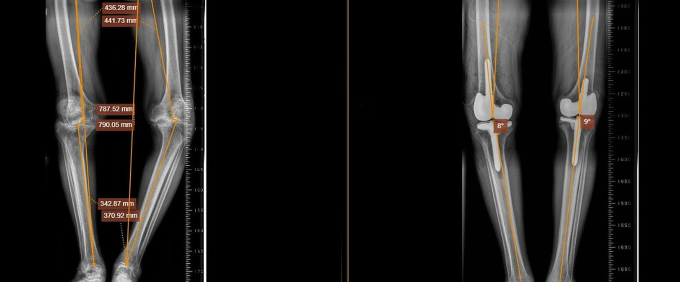

Ông Tri phẫu thuật tái tạo dây chằng chéo trước ở chân trái hơn 10 năm trước, sau đó khớp gối không ổn định, hai chân cong vẹo. Ông điều trị bằng nhiều phương pháp như dùng thuốc theo đường uống, tiêm, tập vật lý trị liệu… Kết quả chụp X-quang tại Bệnh viện Đa khoa Tâm Anh TP HCM cho thấy ông Tri bị thoái hóa khớp gối nặng cả hai chân, chân trái vẹo trong hơn 30 độ và chân phải vẹo ngoài hơn 10 độ. Bệnh kéo dài làm sụn khớp gần như không còn, khiến các đầu xương bị cọ xát, gây mất xương, co rút dây chằng trong và thay đổi trục khớp gối, dẫn đến biến dạng chân.

Phim chụp X-quang hai chân ông Tri trước (trái) và sau khi thay khớp. Ảnh: Bệnh viện Đa khoa Tâm Anh